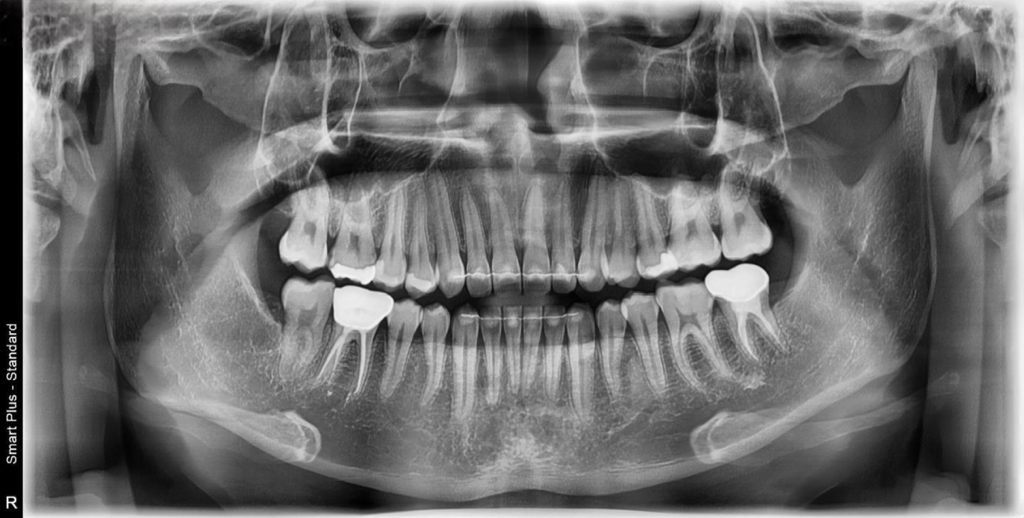

치아 번호로 말씀드리면 24번 27번 인레이 치료(필수) + 25,26번 레진(인레이 치료 도중 충치 발견시 레진 치료 가능성 높음) + 45번 치아 마모된 부분 레진 치료 이렇게 진단을 받았습니다.

참고로 위 치아들에서 통증은 전혀 느껴지지 않았고 45번 치아에 치과 바람 기계? 쏠 때만 시림을 느꼈습니다.

파노라마 사진만 가지고는 정확한 진단이 불가능 하기 때문에

엑스레이 상으로만은 정확히 판단은 어렵지만, 26, 27번사이에 약간 충치가 잇어 보이긴합니다. 24번은 치아가 겹쳐 보여서 엑스레이 상으로는 확ㅇㄴ이 어렵네요. 그리고 45번의 경우는 시리다면 치경부 치료를 하시는게 좋습니다.